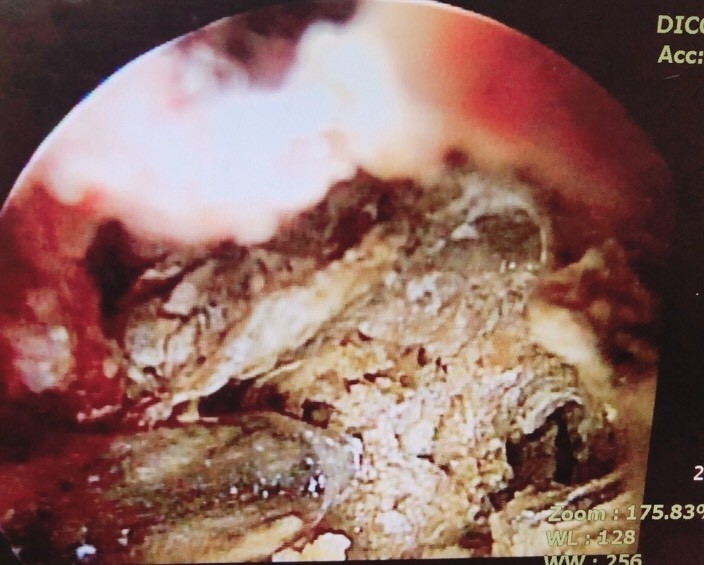

內視鏡潛入泌尿道,發現男大生的泌尿道有如「礦坑」。(記者王捷翻攝)

〔記者王捷/台南報導〕一名男大生最近尿出茶色尿液、腹痛難忍,決定到安南醫院就診

,在檢查後醫師發現男大生的泌尿道簡直像「礦坑」,短短泌尿道內就有約6顆0.5公分的

結石,這時男大生才說,他每天至少喝3杯手搖杯飲料,他知道喝太多糖不好,也會點無

糖飲料,以為可以取代水,醫師一聽規勸,別以為喝了無糖飲料就沒事!